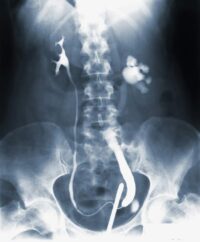

Renal Stone (Kidney Stone)

Renal stones are hard mineral deposits that form in the kidneys and can cause severe pain when passing through the urinary tract. Symptoms include sharp back or abdominal pain, blood in urine, nausea, and frequent urination. Diagnosis is done via ultrasound, CT scan, or X-rays. Treatment ranges from hydration and pain relief to procedures like lithotripsy or surgical removal. We provide expert care and dietary counseling to prevent recurrence. Timely management avoids complications like infection or kidney damage.